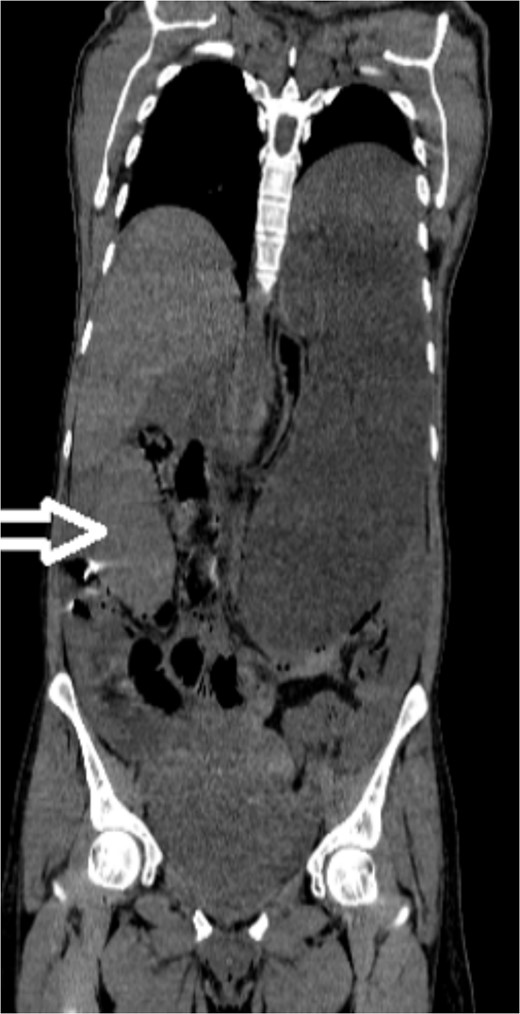

Upon admission to our hospital, the patient’s physical examination revealed hypotension (87/52 mmHg) and tachycardia (150 bpm), along with marked diffuse abdominal tenderness and guarding. Laboratory investigations indicated a hemoglobin level of 7.1 g/dl, a white blood cell count of 14.5 × 103 μl, and a platelet count of 202 × 103 μl. An abdominal CT scan without contrast showed an enlarged ectopic spleen measuring 18 cm in the right abdominal area, a distended stomach, a moderate volume of hemoperitoneum, and significant intra-abdominal fluid accumulation. CT findings are shown in Figs 1–3. Based on these findings, the patient was immediately transferred to the operating room.

Noncontrast coronal CT scan of the abdominopelvic area showing the spleen located in the right upper abdominal area.

In the diagnosis of wandering spleen, noncontrast-enhanced CT scans are invaluable, especially in emergent settings where contrast use may be avoided due to patient instability or renal impairment [14]. In our case, the use of noncontrast CT was pivotal in identifying the ectopic location of the spleen and the extent of the hematoma, although it limited detailed assessment of vascular structures. Nonetheless, we opted for a contrast-free scan due to the patient’s instability.